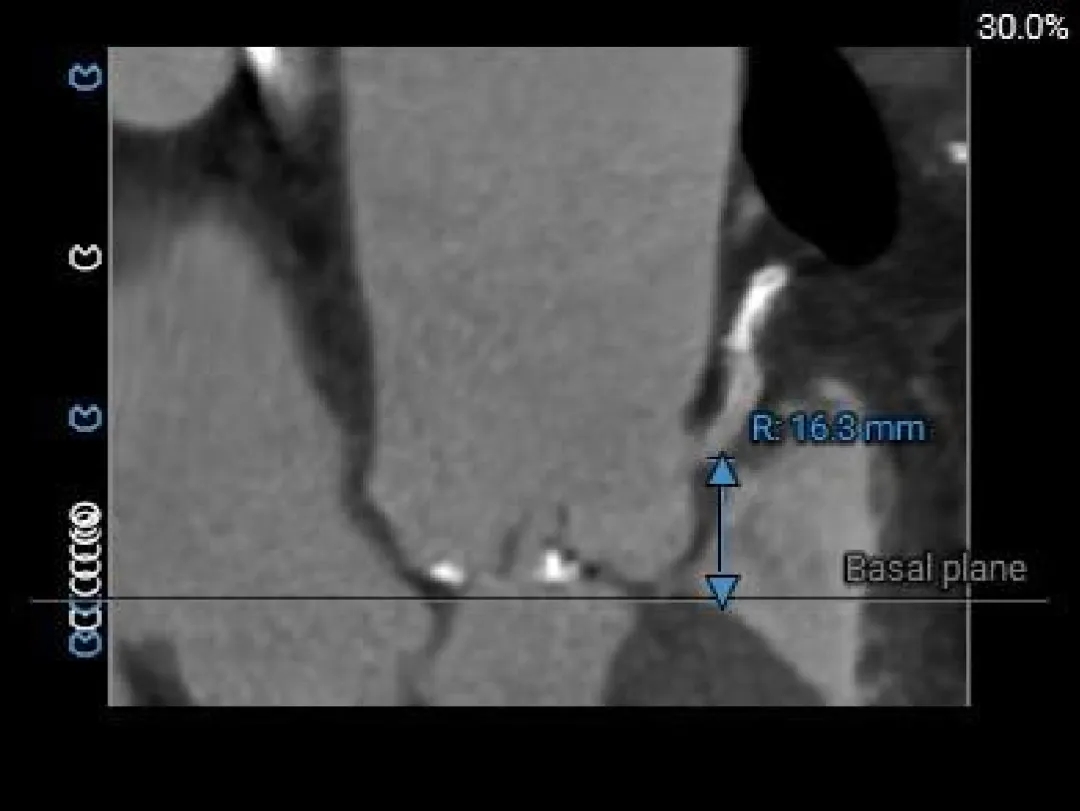

瓣上结构测量

Super-Annulus 2mm 23.2mm

Super-Annulus 4mm 23.4mm

Super-Annulus 6mm 24.2mm

Super-Annulus 8mm 24.7mm

左室测量

心室内径尚可

心室壁增厚

68°横位心